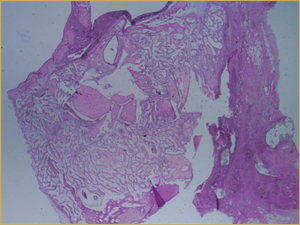

After 2 weeks, grafted mature cortical bone fragments were present in the rabbit maxillary sinuses augmented with autogenous bone grafts (Fig. 3a). Few lacunae within the grafted bone were occupied by osteocytes (Fig. 3b). The margins of the grafted particles demonstrated active bone turnover and remodelling. Resorption of the grafted mature cortical bone was coupled with areas of newly formed woven bone. The new bony regenerate demonstrated plump osteocytes and osteoblasts.

Figure 3a: Low-power histologic examination of rabbit maxillary sinus augmented with autogenous bone graft at 2 weeks after grafting. Hematoxylin and eosin (H&E) stain, 50× magnification.